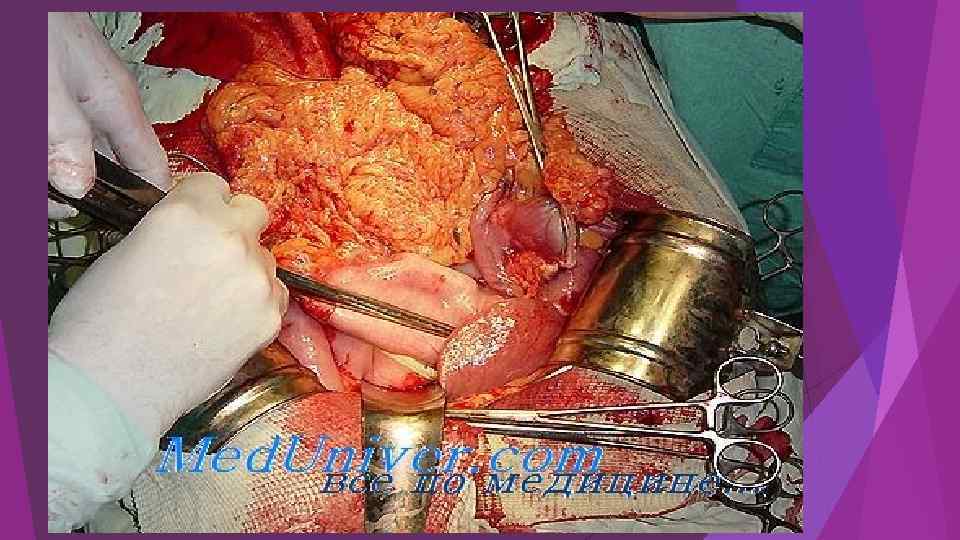

Вскрытие сальниковой сумки и секвестрэктомия при инфицированном распространенном панкреонекрозе Балалыкин А. С. , Луцевич О. Э. , Галлямов Э. А. , 2007

Вскрытие сальниковой сумки и секвестрэктомия при инфицированном распространенном панкреонекрозе Балалыкин А. С. , Луцевич О. Э. , Галлямов Э. А. , 2007